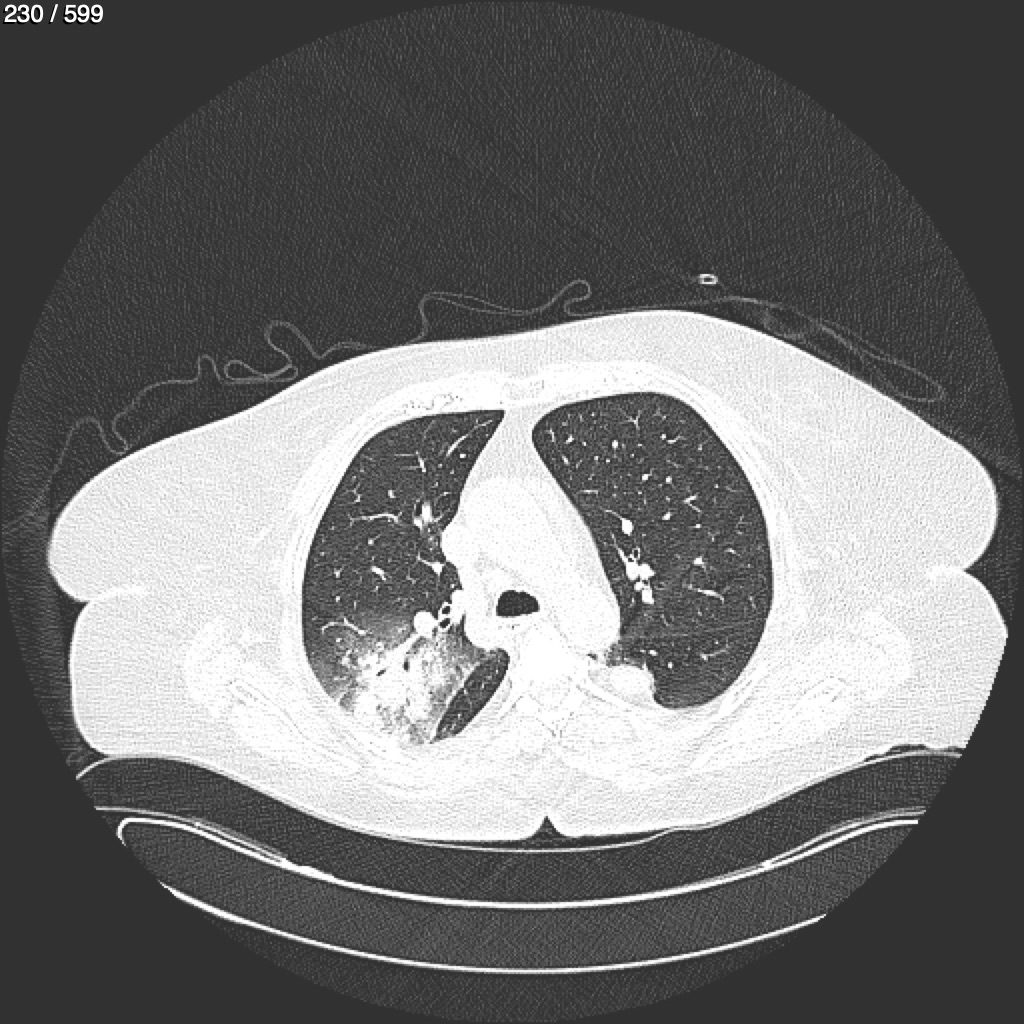

Home G​l​o​r​i​a​ ​G​l​a​d​y​s​ ​B​e​a​s​l​e​y​ ​-​ ​T​ó​r​a​x​ ​T​o​r​a​x​_​S​i​m​p​l​e​ ​(​A​d​u​l​t​o​)